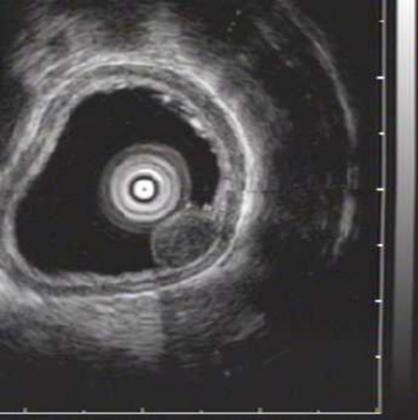

⑦超声胃镜

EUS是将微型高频超声探头安置在内镜前端,在内镜直视观察腔内形态的同时,又可进行实时超声扫描近距离探查,使靶器官的结构与图像更为清楚,为临床治疗方案的选择提供了有力的支持。我院消化内镜于2004年在四川省率先开展EUS新技术,目前拥有国内最新—代的EUS系统,它集超声内镜主机、高频小探头、三维超声探头、环扫内镜超声等 先进设备为—体。我院EUS诊疗组,现有教授1名、副教授2名,每年完成近千例消化道EUS诊疗,EUS诊疗技术达到省内先进水平。

正常食道

食道平滑肌瘤

食道粘膜肌层平滑肌瘤

异位胰腺

脂肪瘤

间质瘤

胰头癌

胆总管结石

为什么需要EUS

普通内镜检查只能发现消化道表面的病灶,通过EUS显示消化管壁层次结构及周围脏器病变,能更准确判断胃肠隆起病变的 性质、来源、肿瘤的浸润深度,还能取活检,指导确定治疗方案及判断疗效。

EUS适应症

1、消化道肿瘤的诊断,术前分期、术后随访

2、判断粘膜下肿瘤的起源与性质

3、胰腺与胆道疾病的诊断与鉴别

4、食管胃底静脉曲张的诊断与疗效判断

5、溃疡性病变良恶性的判断

6、各种需要EUS介入治疗的疾病